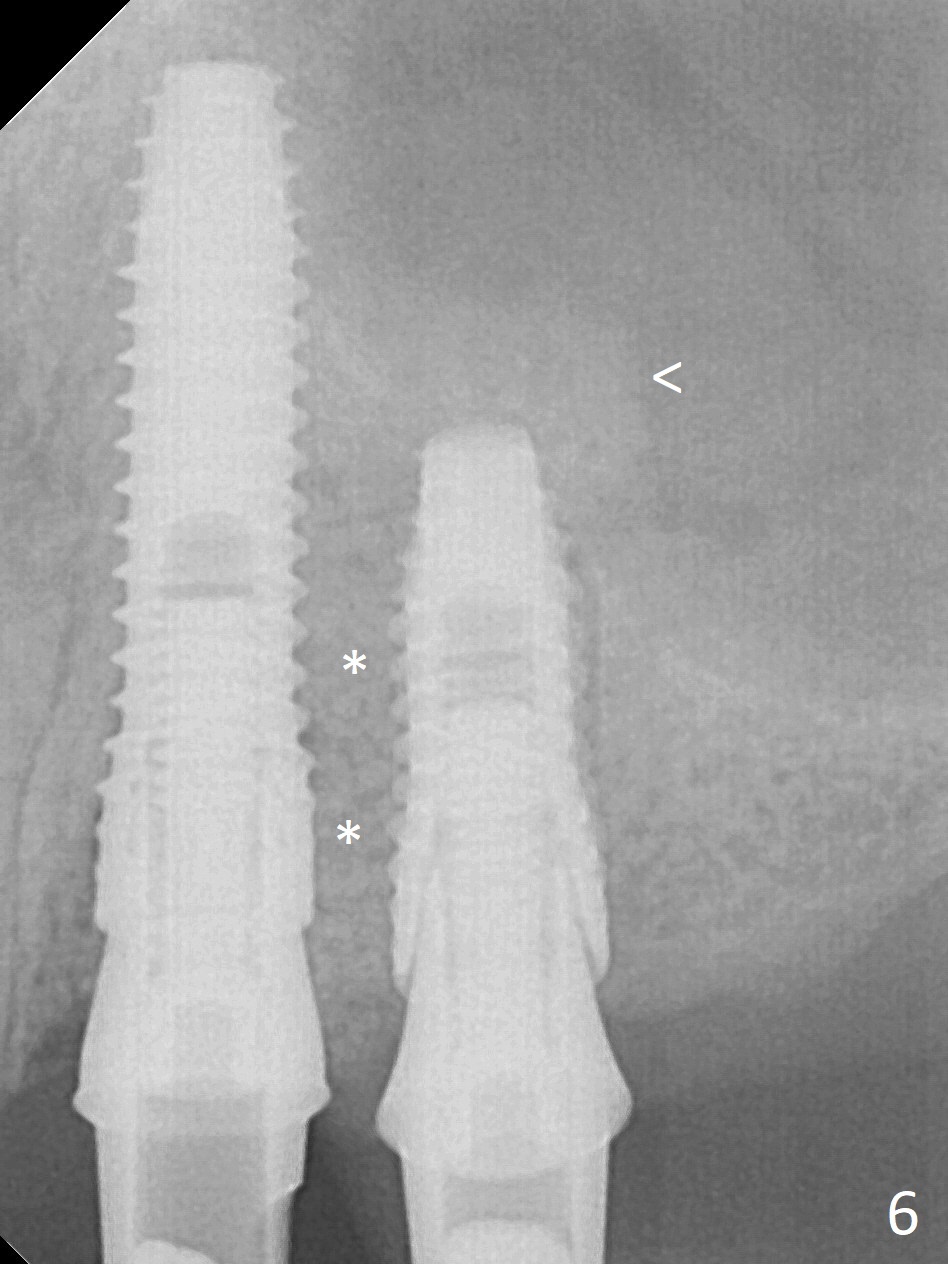

The buccal gingiva at #12 with vertical root fracture looks unhealthy (Fig.1). Osteotomy at #13 is initiated prior to #12 extraction. In fact the osteotomy happens in the extensive defect associated with #12 (Fig.2 red dashed line). To obtain primary stability, the osteotomy at #12 needs to be long, while that at #13 needs two-pointed fixation (Fig.3 *). After adjustment of trajectory at #12 and increase in diameter of the osteotomy at #13 (Fig.4), a 3.8x15 and 3.8x10 mm implants are placed (Fig.5). Following adjustment of implant depth (Fig.6), the implant at #12 becomes loose, while that at #13 tightens. With placement of abutments, an immediate splinted provisional is locked in place to stabilize the loose implant at #12 (Fig.7). The patient complains of cold sensitivity in the upper left quadrant, possibly related to the fact that the implant at #12 is close to the apex of the tooth #11. The position and trajectory of the initial osteotomies should be changed as shown in Fig.8 (white lines, as compared to Fig.2). There is no sensitivity 1 month postop. Impression is taken 4 months postop (Fig.9) after #13 mesiobuccal margin prep. The implants were placed too close to each other. The abutment screw at #13 is retightened 8 months post cementation. There appears no bone loss 9 months post cementation (Fig.10), while the tooth #11 has periapical infection with DL caries 1 year 7 months post cementation (Fig.11).